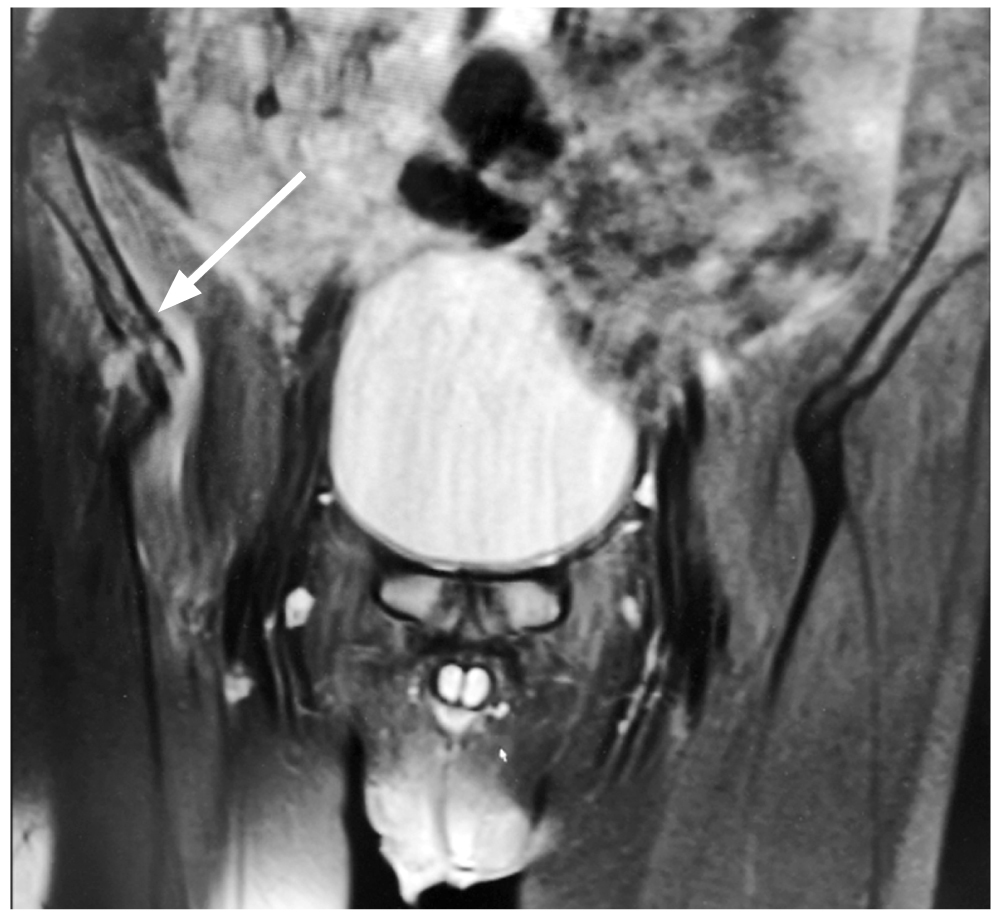

В 3 случае мальчику 10 лет на 5 сут болезни с болями и ограничением амплитуды движений в правом тазобедренном суставе после УЗИ (заподозрена псоас-гематома) выполнено МРТ, где кроме отёка ягодичных и подвздошной мышц справа, вероятно воспалительного характера, описан локальный отёк субхондральной поверхности правой подвздошной кости (рис. 4).

Рис. 4. Магнитно-резонансная томография правой подвздошной кости (мальчик 10 лет, 5 сут заболевания, фронтальная плоскость, Т2-взвешенное изображение): локальный отёк субхондральной поверхности правой подвздошной кости (стрелка).

Fig. 4. MRI of the acute hematogenic osteomyelitis of the right iliac bone (front plane, T2-weighted imaging) in a 10-y.o. child on day 5 of the disease. Local edema of subchondral surface of the right iliac bone (arrow).

Интраоперационно под надкостницей обнаружен гной (S. aureus в титре 105 КОЕ/мл), подтверждён диагноз «ОГО правой подвздошной кости; параоссальная флегмона».